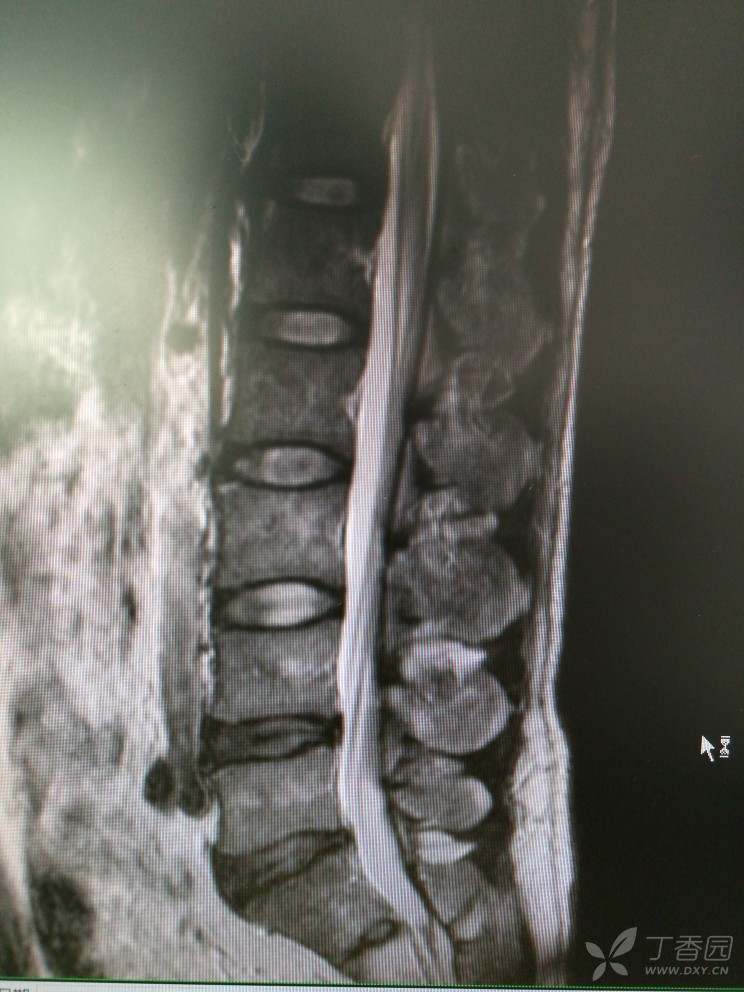

双下肢麻木查因

患者男,46岁,双下肢麻木2年余。

2年前无明显诱因出现双下肢麻木,双下肢沉重感,感觉对称,在坐位、平卧位时发生,活动或抬高下肢后缓解,无双下肢放射痛及乏力等。

查体:腰椎活动可,腰肌稍紧,L2-S1椎无明显压痛,双侧坐骨行程无压痛,直腿抬高试验(-),加强试验(-)肌力5级,肌张力正常,生理反射存在,病理反射未引出。

入院查MRI

我想问还是考虑L4/5 L5/S1椎间盘的变性引起的吗?